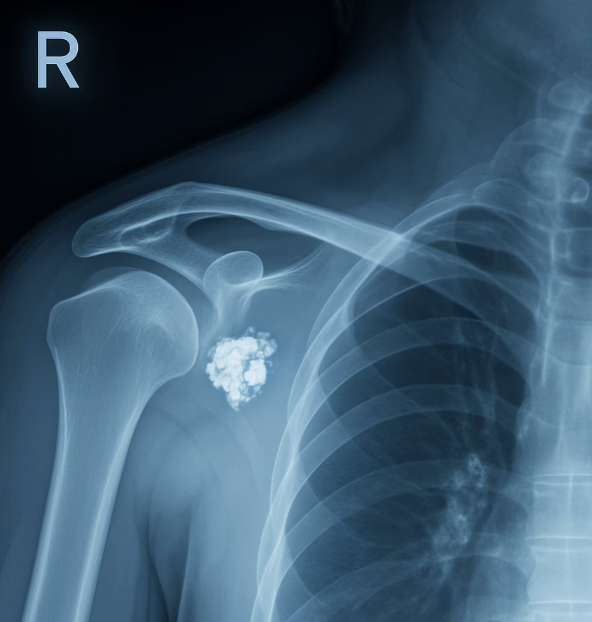

차이점 3: X-ray에 나타나는 '결정적 증거'

마지막으로, 두 질환을 가장 명확하게 구분할 수 있는 방법은 바로 'X-ray 검사'입니다. 오십견은 관절 주머니의 염증이라, 일반 X-ray 사진에서는 뼈에 아무런 이상이 없는 '정상' 소견으로 나타납니다. 그래서 "뼈에는 이상이 없으니, 오십견이네요" 라는 진단을 받게 되는 것이죠.

하지만 석회성건염은 다릅니다. X-ray를 찍어보면, 어깨 힘줄 부위에 마치 하얀 분필 가루나 조개껍데기처럼 보이는 '석회 덩어리'의 그림자가 아주 선명하게 나타납니다. 이 하얀 그림자야말로 통증의 원인이 바로 석회임을 증명하는, 빼도 박도 못하는 '결정적 증거'가 됩니다. 따라서 극심한 어깨 통증으로 병원을 찾았다면, X-ray 검사를 통해 이 '돌멩이'의 존재를 확인하는 것이 진단의 첫걸음입니다.